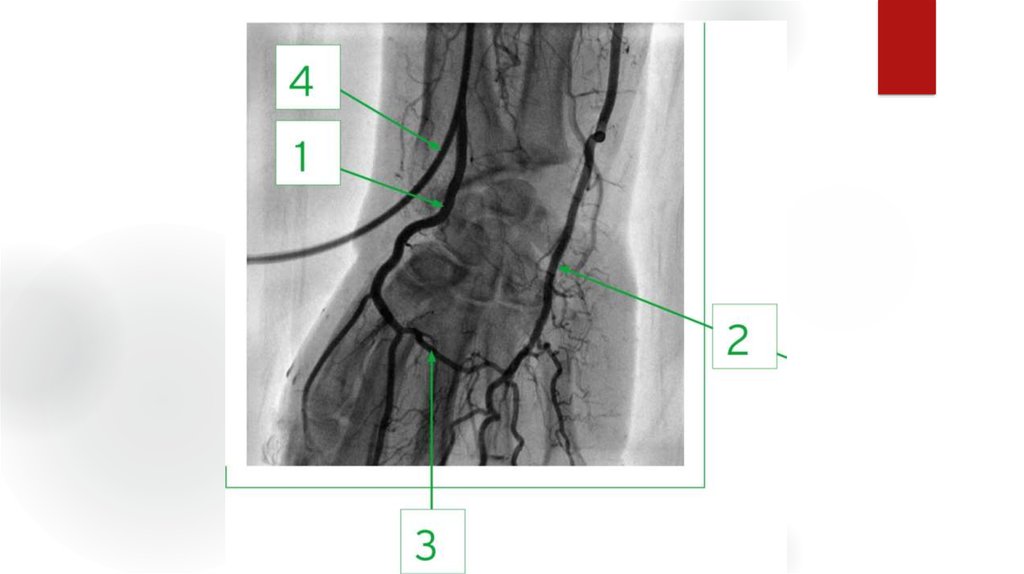

24. Оценка ангиограмм

Критерии:

- Окклюзии, их локализация

- Сегментарный уровень

- Степень

- Длинна пораженного участка

- Конфигурация и анатомия

- Количество пораженных артерий

- Морф.тип стеноза

- коллатеральное кровообращение